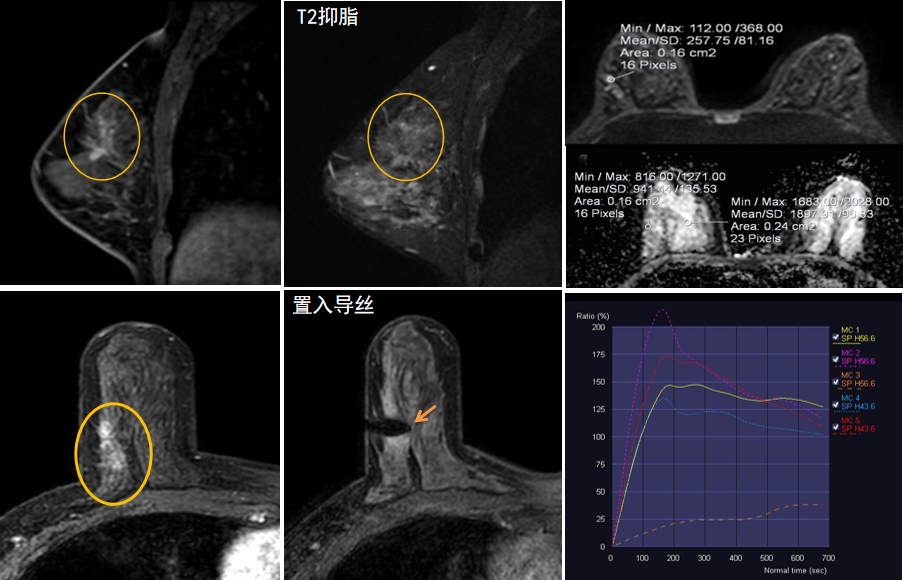

今年45歲的某女士,兩個(gè)月前行超聲檢查發(fā)現(xiàn)右乳結(jié)節(jié),乳腺X線攝影檢查提示右乳外上象限局部腺體結(jié)構(gòu)扭曲并簇狀無(wú)定形鈣化,為了進(jìn)一步評(píng)估病變性質(zhì)并確定范圍進(jìn)行了乳腺M(fèi)R平掃 DWI 增強(qiáng)的檢查,經(jīng)MR評(píng)估發(fā)現(xiàn)右乳病變范圍較廣,評(píng)估為BI-RADS 4類可疑病變,需要取得病理學(xué)結(jié)果。

陳寶瑩主任及其帶領(lǐng)的MR介入診療小組詳細(xì)詢問(wèn)了病情,分析了患者資料,并與患者和臨床醫(yī)生進(jìn)行了充分溝通,確定于手術(shù)前為患者實(shí)施MR引導(dǎo)下的病變穿刺導(dǎo)絲定位和體表范圍確定。手術(shù)前陳寶瑩主任帶領(lǐng)聶品醫(yī)師、馬小偉技師、韓愛(ài)萍護(hù)士長(zhǎng)等MR介入診療小組成員,借助MR高清的圖像顯示和定位系統(tǒng),確定病變范圍,精準(zhǔn)穿刺置入定位導(dǎo)絲,并準(zhǔn)確標(biāo)記出病變體表范圍,整個(gè)過(guò)程患者無(wú)任何不適。在定位導(dǎo)絲和體表范圍標(biāo)記的輔助下,甲乳外科劉曉敏主任精準(zhǔn)切除了病變,解除了患者的后顧之憂。

國(guó)內(nèi)外指南均建議40歲以上的女性每年行一次雙乳X線攝影(鉬靶)檢查,以篩查乳腺癌。對(duì)于乳腺癌高危人群40歲以前即建議開(kāi)始乳腺癌篩查,除了進(jìn)行乳腺X線攝影(鉬靶)篩查外需要補(bǔ)充MR檢查,MR檢查敏感性最高,能夠發(fā)現(xiàn)大量X線攝影和超聲檢查陰性的可疑病變,基于多模態(tài)、多參數(shù)的結(jié)構(gòu)和功能成像的基礎(chǔ)上,MR能夠精準(zhǔn)顯示病變位置、范圍以及病變內(nèi)的活性區(qū)域,MR引導(dǎo)下的介入診療不但解決了僅在MR顯示的病變的處置難題,而且能夠精準(zhǔn)定位活性區(qū)域,保證了定位、活檢及旋切的準(zhǔn)確性。